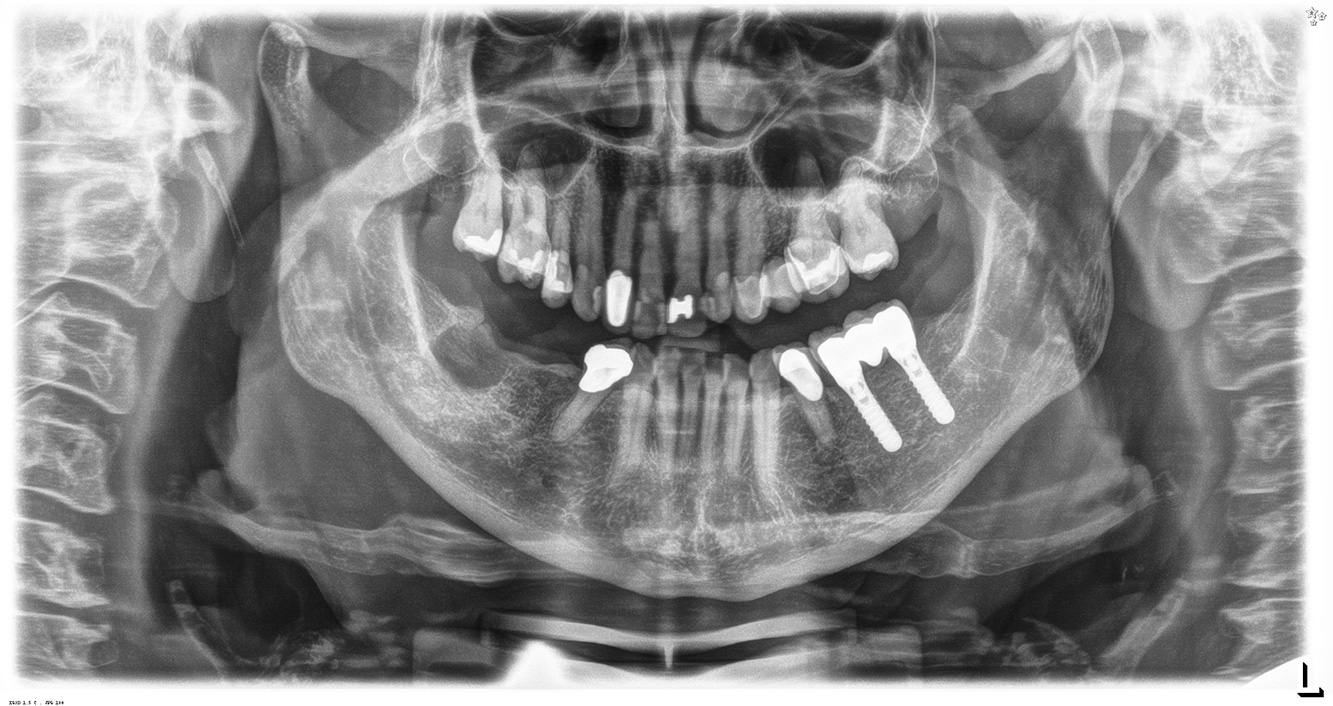

The healthy patient with pre-existing periodontal disease & peri-implantitis

A 52-year-old patient presents at a preventive care session. The patient has no systemic disease and is not taking any medication. He has had various dental treatments and also has two active carious lesions. In addition, the patient has four implants (2nd, 3rd and 4th quadrants). He is revealed to have early periodontal disease (stage IV, grade B). His periodontal condition is stable; a probing depth of Probing depths (ST) of 5 mm is only evident at the implant in region 36. Gingivitis is also identified. more

Pacientul în vârstă de 68 de ani nu are nicio afecțiune generală și nu ia niciun medicament care ar putea fi relevant pentru sănătatea sa orală, iar stilul său de viață nu prezintă niciun risc special. Pacientul are două implanturi dentare (cadranul 3, de cinci ani) și un caz anterior de boală parodontală (stadiul IV, gradul B) cu pierderea dinților. În prezent, condițiile parodontale sunt stabile. Cu toate acestea, parodontoza crește semnificativ complicațiile biologice ale implanturilor și există riscul de pierdere a implanturilor (21). Se pot determina patru recomandări pentru ședința de profilaxie. mai multe